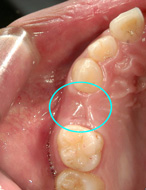

17才の女性。主訴は「乳歯が抜けたあと、永久歯が生えてきません」=写真左=でした。

まず、永久歯が生えてこない状態のことを「先天性の永久歯欠損」といいます。原因は、生まれつき大人の歯の数が少ないため、乳歯が抜けたあとに歯が生えてこないのです。このような場合、3通り(インプラント/ブリッジ/入れ歯)の治療方法があります。

まずは、インプラント治療。これならブリッジ治療のように、両サイドの白い歯を削る必要はありません。また入れ歯のような装着時の違和感もありません。「インプラント=ベストの選択」と言いたいところですが、この患者様の年齢(17歳)を考えますとインプラント治療の時期はまだ早い(あご骨が成長途中のため)と考えられます。

残り、「ブリッジ」と「入れ歯」のどちらを選択すればいいのでしょうか?